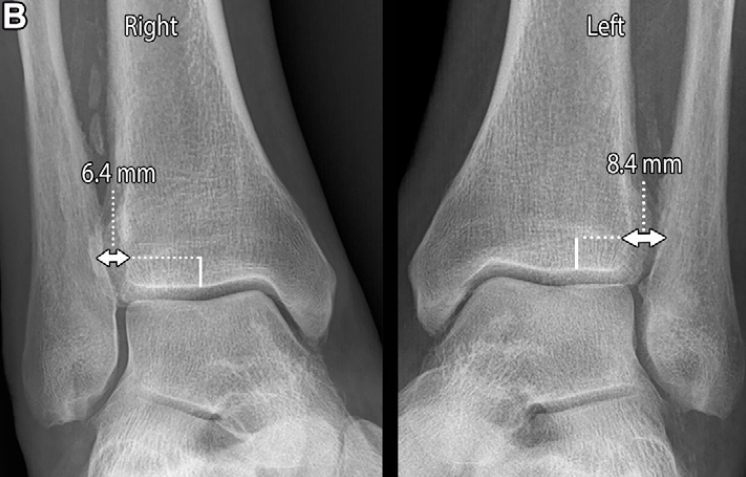

X线片评估胫腓联合分离可通过三项核心测量指标:胫腓重叠距离、胫腓间隙宽度和内侧间隙宽度:

胫腓重叠距离指腓骨远端内侧缘与胫骨远端前结节之间的水平距离,测量点位于胫骨关节面上方10mm处;正位片上该值大于6mm、踝穴位上大于1mm为正常范围 。胫腓重叠距离缺如可能是正常的解剖变异,但踝关节损伤后若出现单侧缺如,应考虑为胫腓联合分离的征象。

胫腓间隙宽度指胫骨后结节外侧缘与腓骨沟最深点内侧缘之间的水平距离,在正位和踝穴位上于胫骨关节面上方10mm处测量,该值≤6mm 为正常;患侧与健侧的胫腓间隙宽度差值≥2mm,可能提示胫腓联合损伤。